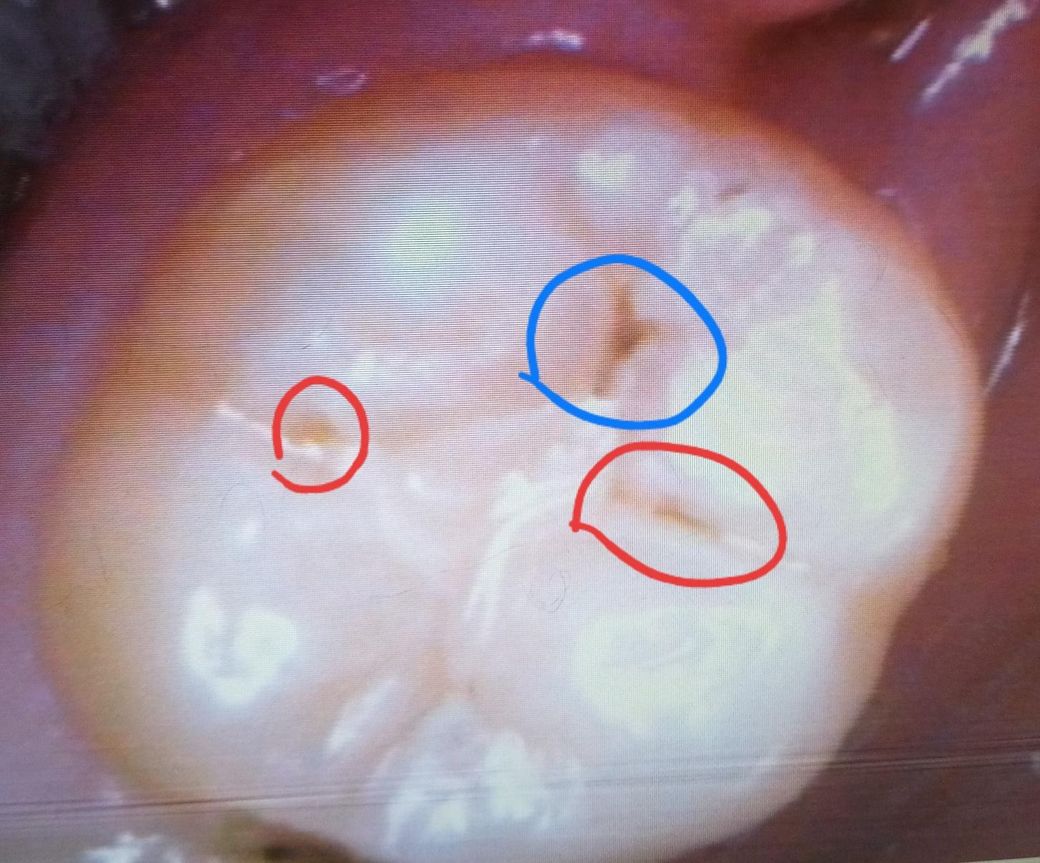

파란색 부분은 처음부터 레진하지 않은 곳이고

뻘간 동그라미 부분이 레진하고 벗겨진 부분이에요.

*의사쌤 답변 : 빨간 동그라마,파란 동그라미 부분 정지우식,C1임 그러니 괜찮다. 그리고 저기 다 할려면 인레인해야 할수있다.

• 1번 째 사진